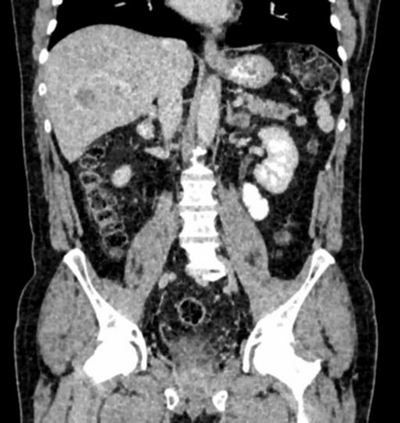

Due to the constraints of the imaging device and high cost in operation time, computer tomography (CT) scans are usually acquired with low intra-slice resolution. Improving the intra-slice resolution is beneficial to the disease diagnosis for both human experts and computer-aided systems. To this end, this paper builds a novel medical slice synthesis to increase the between-slice resolution. Considering that the ground-truth intermediate medical slices are always absent in clinical practice, we introduce the incremental cross-view mutual distillation strategy to accomplish this task in the self-supervised learning manner. Specifically, we model this problem from three different views: slice-wise interpolation from axial view and pixel-wise interpolation from coronal and sagittal views. Under this circumstance, the models learned from different views can distill valuable knowledge to guide the learning processes of each other. We can repeat this process to make the models synthesize intermediate slice data with increasing inter-slice resolution. To demonstrate the effectiveness of the proposed approach, we conduct comprehensive experiments on a large-scale CT dataset. Quantitative and qualitative comparison results show that our method outperforms state-of-the-art algorithms by clear margins.

翻译:由于成像装置的限制和操作时间成本高,计算机断层扫描通常以低切片分辨率获得。改进切片内分解法有利于人类专家和计算机辅助系统进行疾病诊断。为此,本文件制作了新的医疗切片合成法,以增加解片之间的解析。考虑到临床实践中总是没有地面真相中间医疗切片,我们采用渐进的跨视图相互蒸馏战略,以自我监督的学习方式完成这项任务。具体地说,我们用三种不同的观点来模拟这一问题:从轴视中切片间解法和从正弦和方位角度对等离子间解法。在此情况下,从不同观点中学习的模型可以提取宝贵的知识,用以指导彼此的学习过程。我们可以重复这一过程,使模型合成中间切片数据,同时增加分裂分辨率。为了证明拟议方法的有效性,我们在大规模CT数据集上进行了全面的实验。通过清晰的定量和定性的算法比较结果显示,我们的方法将超越了一种方法。